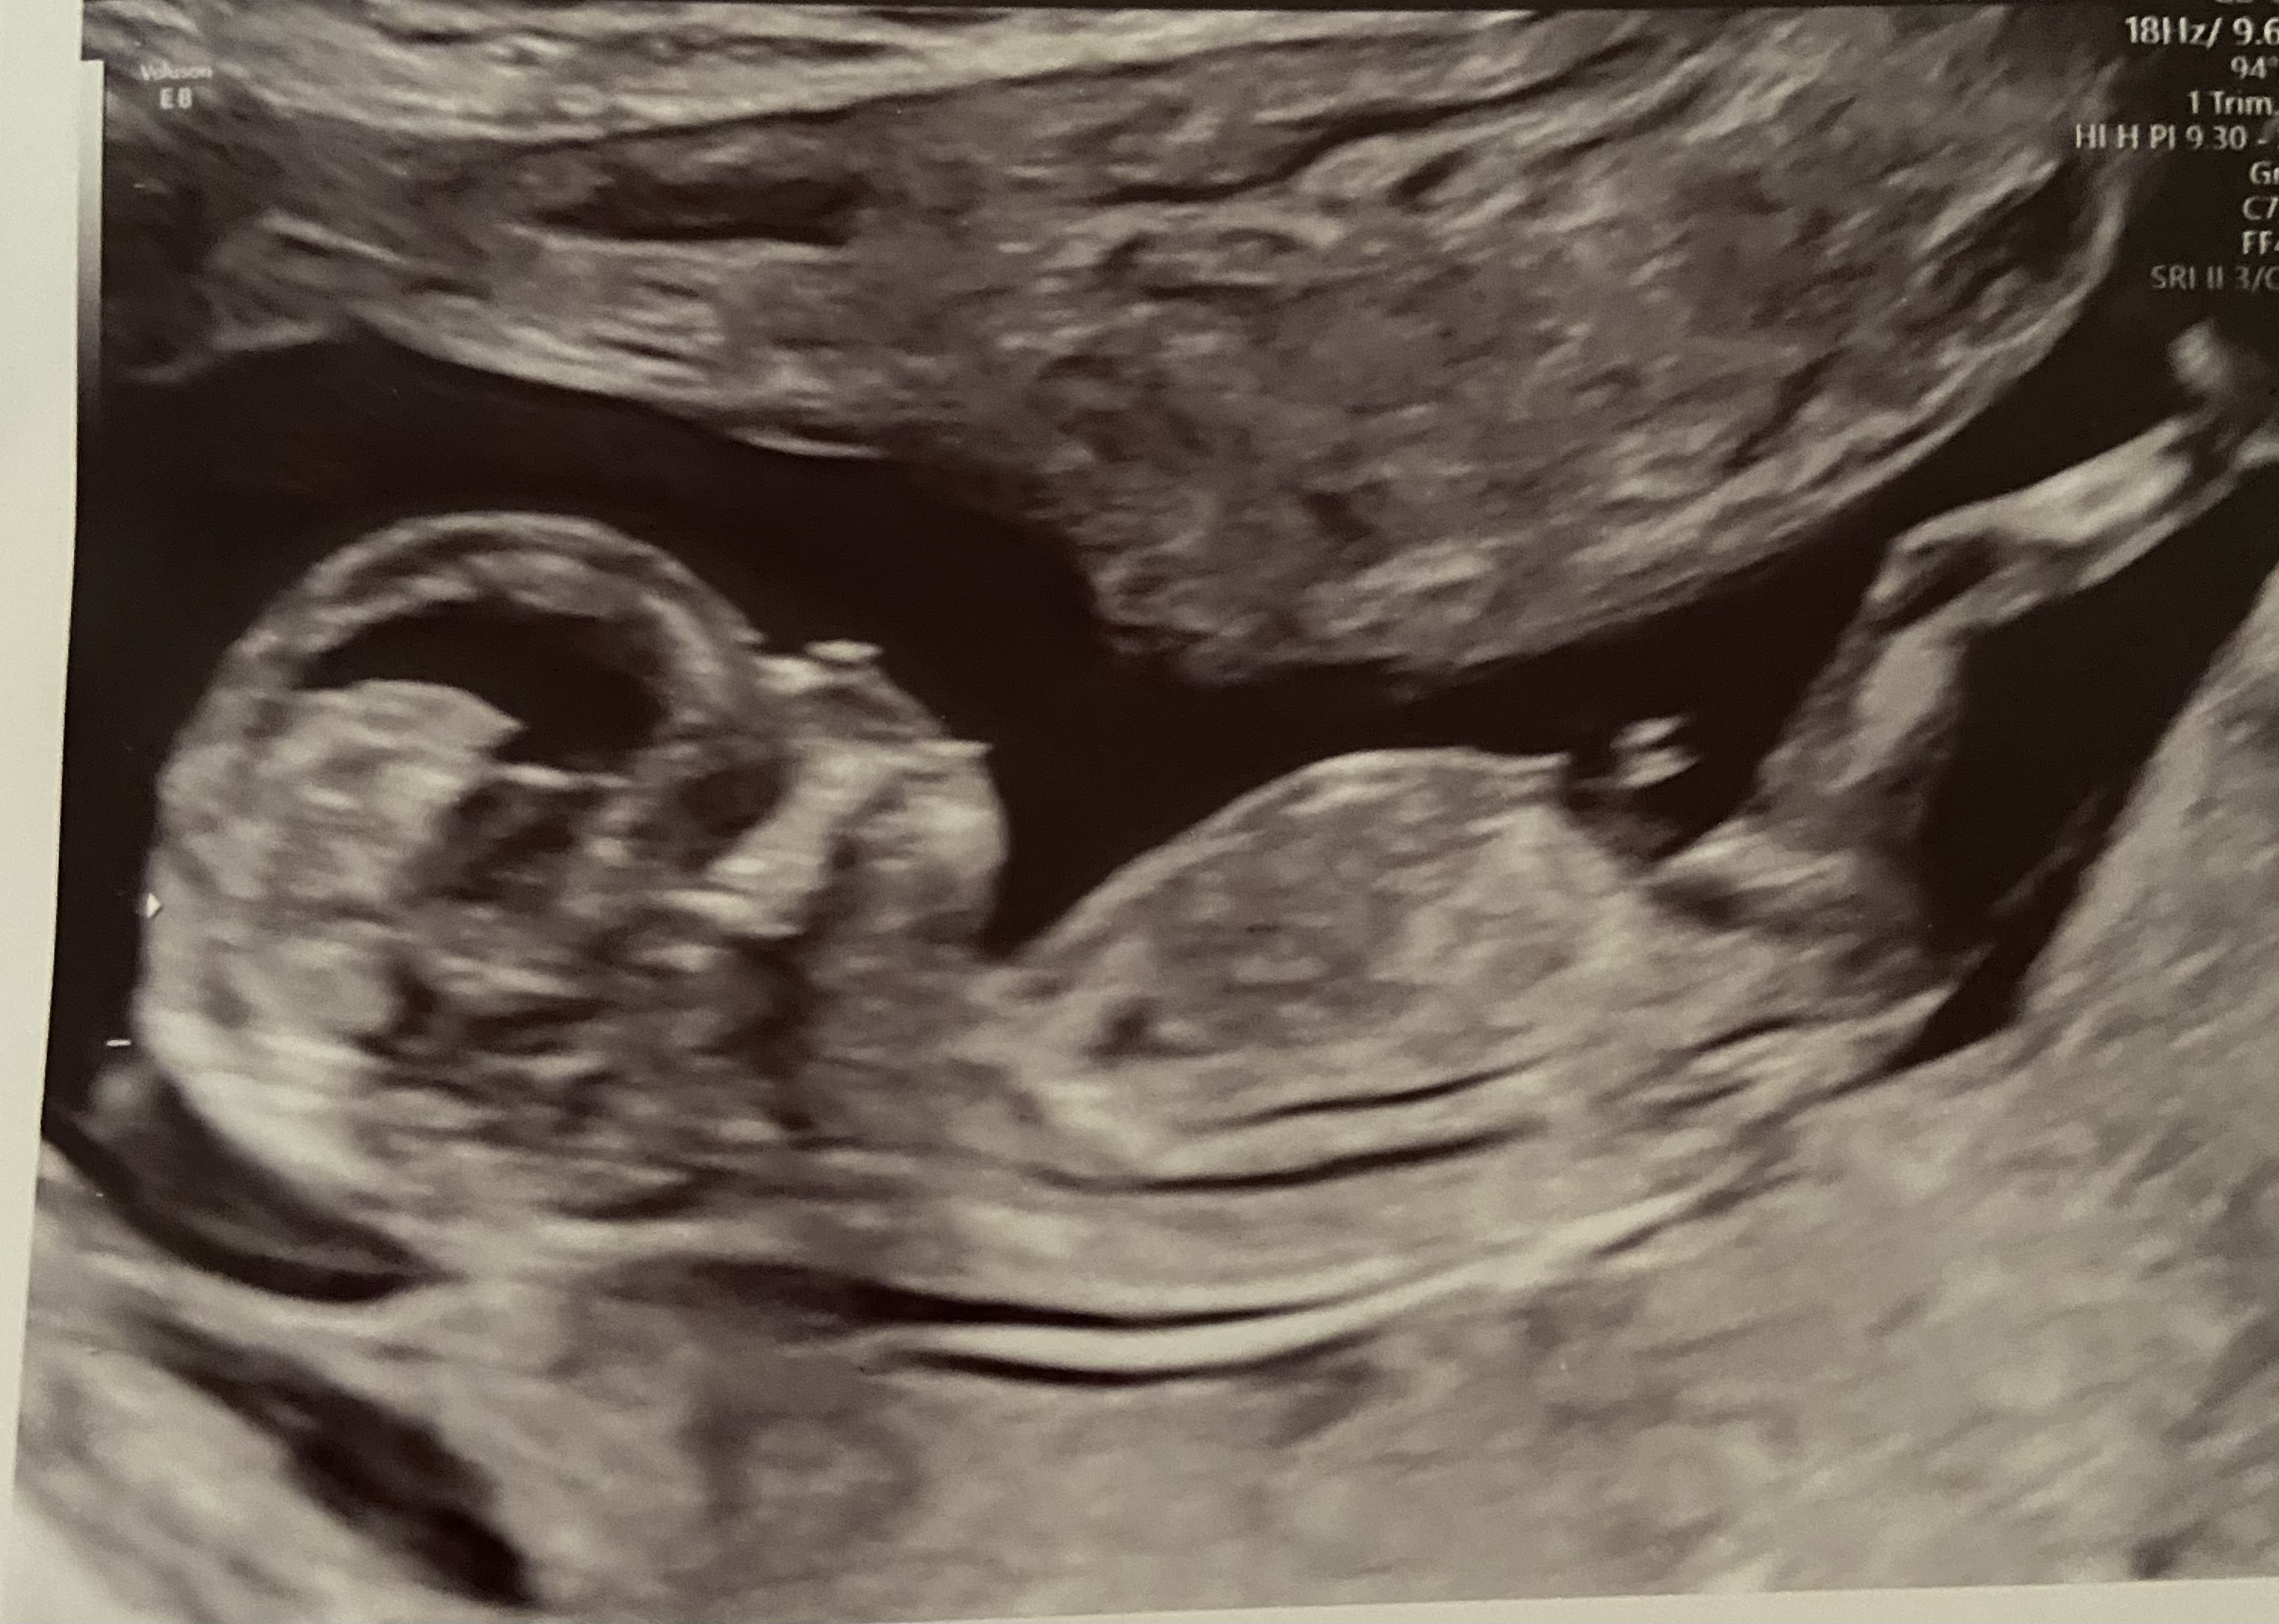

Tentative pink lean, but I'm not real sure to be honest. The top pic looks straight but the end is obscure, the bottom pic also looks straight but "busy". I think the bottom pic is a girl nub but the baby moved and made it look more stacked (the stacking is not in the right place to be real stacking) but it's just not something I can say with any level of certainty.

Baby is a girl!!